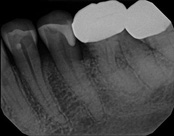

This patient presented with a failed root canal. The root canal became infected. An apicoectomy (apical microsurgery) was performed using the laser. Patient had minimal swelling, minimal discomfort, and fast healing. The tooth was saved and an implant avoided. This tooth tends to have a lower success rate with root canal therapy; thankfully apical microsurgery was available to save the tooth.

At the 3 month follow-up, the gums look like nothing was done thanks to the skill and use of the laser for the procedure.